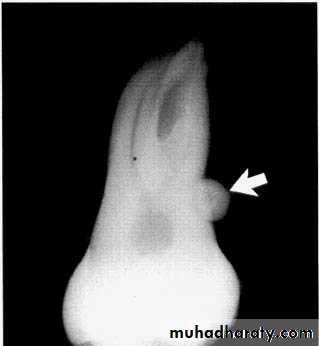

Dilaceration of the crown

specimenX-Ray

Dilacerated root. The apical portion of the root is bent buccally or lingually into the plane of the central ray. Note the halo in the apical region, produced by the PDL

space (arrow).